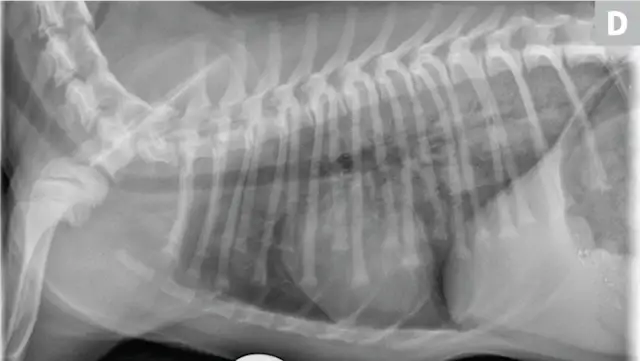

CDV should be suspected in poorly vaccinated dogs with multiorgan involvement. Dogs with CDV may have exhibited only respiratory signs before developing characteristic nonrespiratory signs.12 Radiographs may reveal a diffuse interstitial pattern (Figure 2). Diagnosis is supported by compatible clinical signs and complementary diagnostic testing (ie, real-time reverse transcription polymerase chain reaction [RT-PCR], serology, CSF pleocytosis). Conjunctival scraping and tissue-based immunohistochemistry may confirm diagnosis.

FIGURE 2

CDV pneumonia with a diffuse interstitial pattern confirmed by multisystemic signs, urine RT-PCR, and necropsy